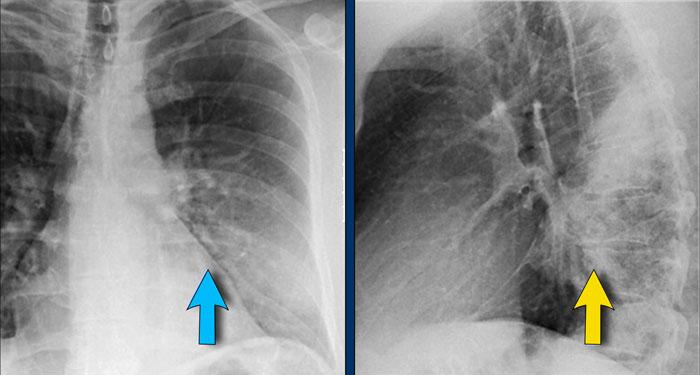

Dấu hiệu Silhouette – Phân tích Phim Nghiêng

Ca lâm sàng 3: Tư thế Nghiêng

- Có tăng độ mờ trên vùng cột sống ngực dưới.

- Phân tích kỹ đường bờ cơ hoành trên phim nghiêng giúp định khu tổn thương:

- Đường bờ vòm hoành phải không quan sát được ở phía sau, gợi ý sự hiện diện của tổn thương có tỷ trọng nước ở thùy dưới phải.

- Tiếp tục xem phim tư thế PA…

Phim PA của Cùng Bệnh nhân

- Bờ tim phải còn nguyên vẹn, xác nhận tổn thương không nằm ở phía trước—phù hợp với phim nghiêng.

- Câu hỏi: Tại sao bóng silhouette của vòm hoành phải vẫn còn nhìn thấy trên phim PA?

- Trả lời: Phần cơ hoành nhìn thấy được trên phim PA đại diện cho điểm cao nhất ở phía trước, vùng này không tiếp xúc với đám viêm phổi ở phía sau thùy dưới phải. Do đó, bóng silhouette bình thường và dấu hiệu silhouette vắng mặt.